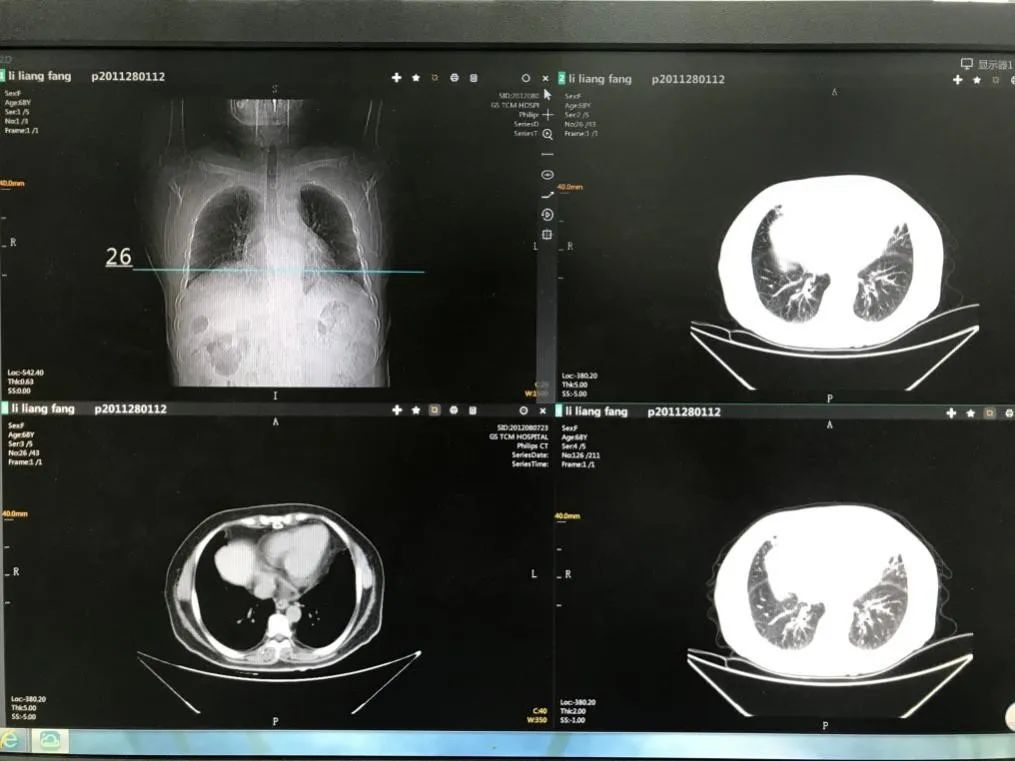

治疗后胸部CT